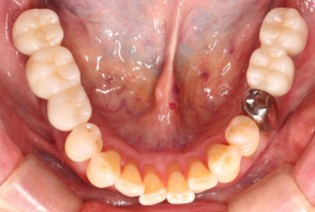

70代 女性

治療前

治療後- リスク・副作用

- 術後疼痛、歯肉腫脹

- 治療の費用

- 合計¥1,126,000(税込)

【内訳】

インプラント(2本)¥880,000

その他費用¥246,000

(薬・注射・レントゲン・ソケットリフト骨造成・サージカルステント・CT・データ分析) - 年齢/性別

- 70代/女性

- 患者の具体的な症状

- 右上56欠損のため義歯を使用していたが不安定で十分噛めないため、インプラント治療を希望

- 検査方法

- コーンビームCT、レントゲン撮影

- 診断結果

- 右上56欠損

- 治療詳細

- 右上56部、コーンビームCTによる画像診断で垂直的な骨高、骨密度の不足のため、ソケットリフトによる骨再生治療とインプラント埋入2本を同時にショートインプラントを用いて行った。

- 通院回数

- 7回

- 治療期間

- 7か月